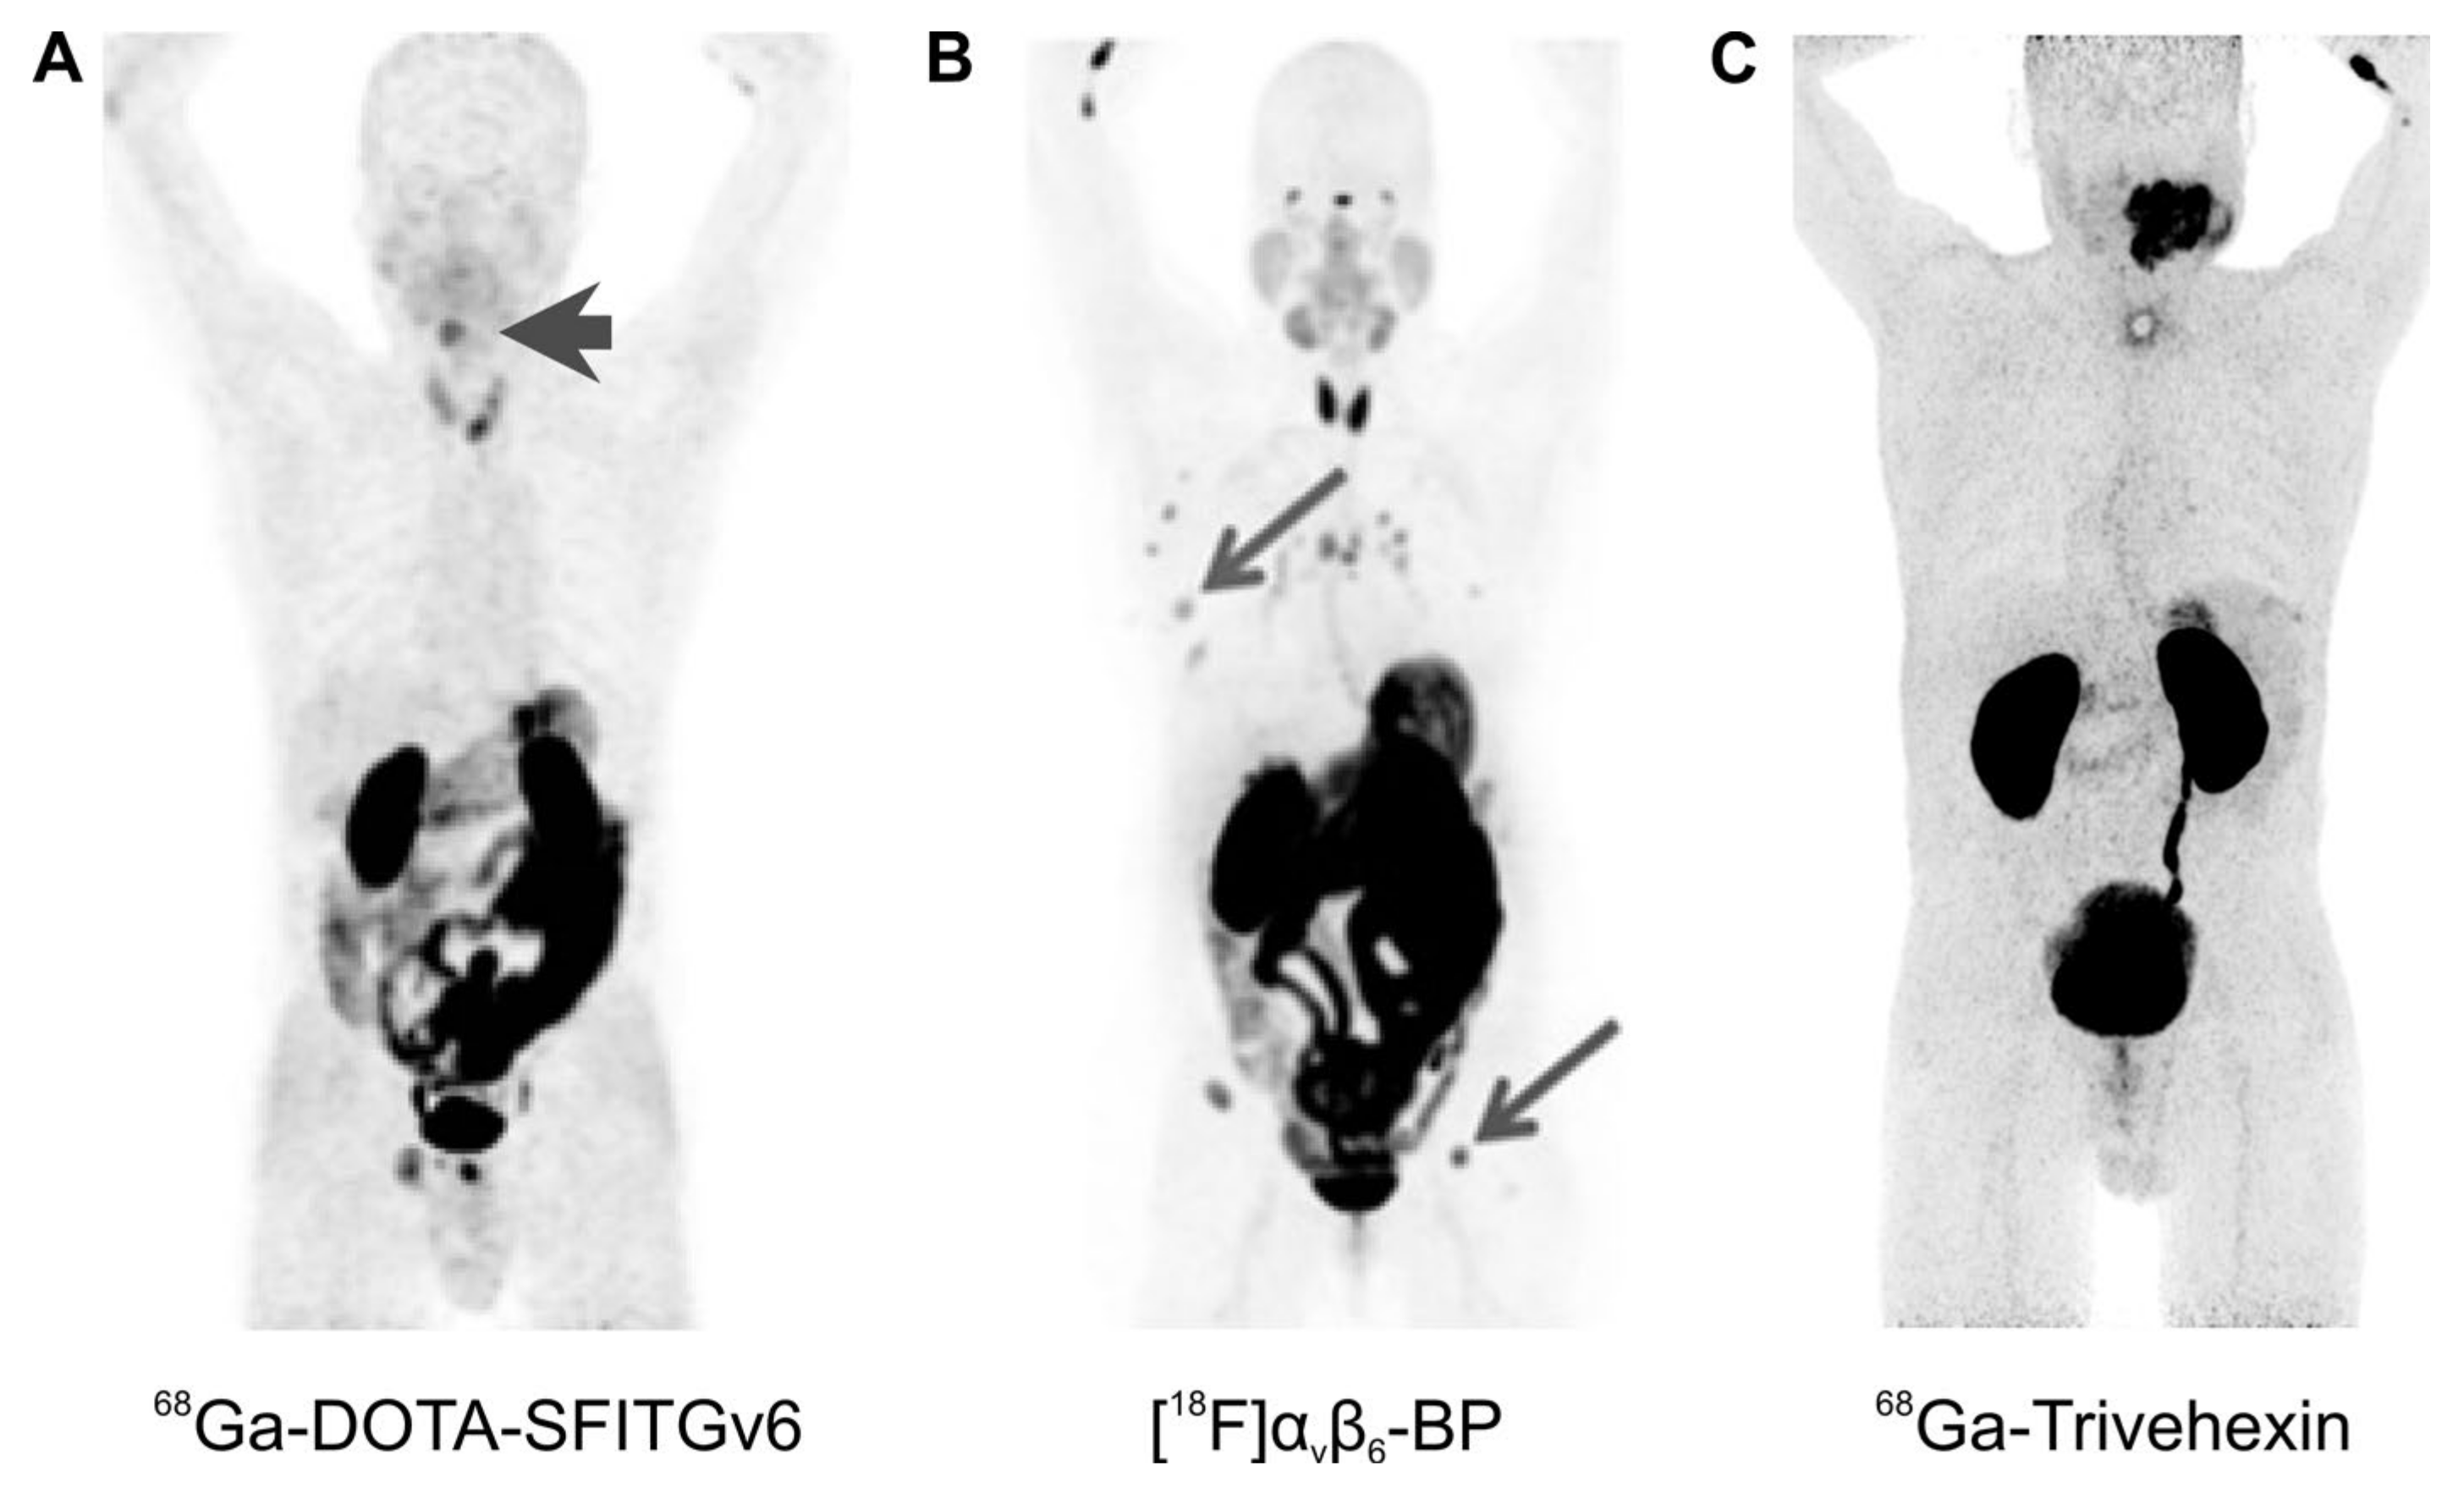

Overall, the hitherto translated PET tracers show predominantly renal clearance; hence, a strong signal is invariantly observed in the kidneys and the urinary bladder (Figure 5 and Figure 6). In addition, some of the agents show more or less prominent non-specific uptake in several organs, most notably, in stomach and intestines. Figure 5 demonstrates that αvβ6-integrin imaging might nevertheless be suitable for visualization of a variety of cancers. This is in accordance with a solid body of evidence that this integrin is expressed in many carcinomas [55]. A particularly high-expression density and, therefore, a high diagnostic relevance of pertinent imaging agents, has been suggested for HNSCC [55]. In line with this notion, a good tumor delineation could be observed for a large sublingual carcinoma using 68Ga-Trivehexin (Figure 5C), and for a hypopharynx tumor using 68Ga-DOTA-SFITGv6 (Figure 5A).

Figure 5.

αvβ6-integrin PET imaging in cancer patients (maximum intensity projections, 1 h p.i.) with different radiopharmaceuticals; arrows (wherever shown) indicate tumor lesions. (A): 68Ga-DOTA-SFITGv6 PET of a recurrent hypopharynx tumor. (B): A stage IV invasive mammary carcinoma, imaged using [18F]αvβ6-BP. (C): 68Ga-Trivehexin PET of a large oral squamous cell carcinoma. Copyright notice: Images were adapted and reprinted from: (A) Clin. Cancer Res. 2017, 23, 4170–4180. Altmann et al., Identification of a Novel ITGαvβ6-Binding Peptide Using Protein Separation and Phage Display [94]; and (B) Clin. Cancer Res. 2019, 25, 1206–1215; Hausner et al., Preclinical Development and First-in-Human Imaging of the Integrin αvβ6 with [18F]αvβ6-Binding Peptide in Metastatic Carcinoma [86]; with permission from AACR and not included in CC-BY 4.0 of this article. (C) Eur. J. Nucl. Med. Mol. Imaging 2021, doi:10.1007/s00259-021-05559-x. Quigley et al., PET/CT imaging of head-and-neck and pancreatic cancer in humans by targeting the “Cancer Integrin” αvβ6 with Ga-68-Trivehexin [105]; under Creative Commons CC BY 4.0.